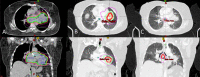

Materials and methods: Between 2008 and present, 10 patients with biopsy proven non-small cell lung cancer (NSCLC) underwent 14 radiosurgical procedures for salvage therapy after failing initial radiation treatment. Patients' age ranged from 54 to 88 years with a median of 74 years in 6 males and 4 females. Intervals from initial radiation treatment to salvage SBRT were 3-33 months with a median of 13 months. SBRT treatments were delivered using Intensity Modulated Volumetric Arc Therapy (VMAT). All patients received concomitant chemotherapy.

Results: Overall survival after salvage radiosurgery ranged from 6 to 41 months (mean 20 months, median 18 months). Four of the ten patients are alive with disease locally controlled. Of the remaining 6 patients, 4 had distant progression of disease with brain metastases and one had both brain and lung metastases. The other patient had a regional failure. Toxicities were found in three of the ten (30%) patients with grade I pneumonitis.